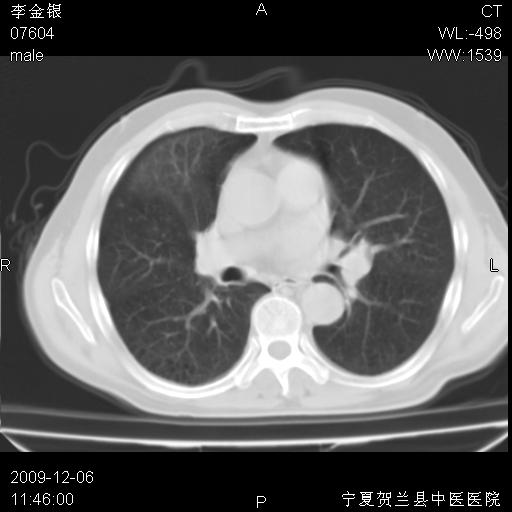

该病人 ,男,62岁,主因咳痰带血两天

考虑右肺中央型占位性病变并阻塞性肺炎.(右肺上叶支气管变窄),建议支纤镜检查.

考虑右肺中心型肺癌伴阻塞性肺炎及右肺门淋巴结转移,建议纤维支气管镜进一步检查。

支气管壁明显增厚 管腔狭窄,腔静脉后多个淋巴肿大,结合年龄病史考虑右肺上叶中央型肺癌并阻塞性肺炎

右肺上叶后段支气管阻塞,右上肺门占位,相应肺段阻塞性肺炎,右肺门有淋巴结肿大。诊断右肺上叶中心型肺癌,阻塞性肺肺炎、右肺门淋巴结转移。

符合中央型肺癌的ct表现并肺出血。但有一点腔静脉后有一钙化的淋巴结啊

右上叶支气管狭窄,管壁增厚,远端斑片状软组织影,病灶邻近叶间裂,叶间裂无移位。

诊断右肺中央型肺癌。

那个片影应该大部分都是病灶,病灶沿肺段支气管分支生长,后段完全显示不清、闭塞。若为不张应该伴有叶裂的移位,若为炎症应有空气支气管征。

右肺中心型肺癌伴阻塞性肺炎及右肺门与纵膈淋巴结转移很典型,可纤维支气管镜进一步检查

考虑右侧中央型肺癌伴右肺上叶后段阻塞性炎症、肺不张、右肺门和纵隔淋巴结肿大。

右肺上叶中心型肺癌,阻塞性肺炎、右肺门和纵隔淋巴结转移。